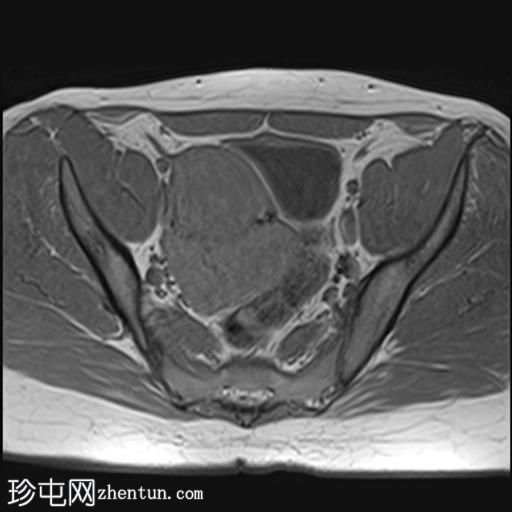

轴位

T2加权像

其中一个位于子宫上方,T2加权像呈中等信号,中心区域呈高信号,增强T1脂肪抑制像未见强化。右侧卵巢增大,增厚的血管蒂扭曲,未见强化,轴位和矢状位T2加权像均显示清晰。